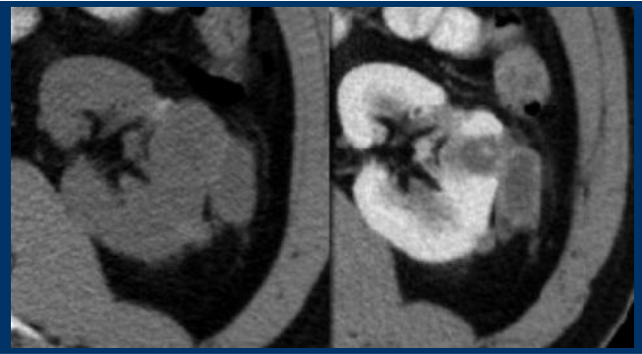

bosniak classifcation?

2F

bosniak classification?

bosniak I

no septa, very simple